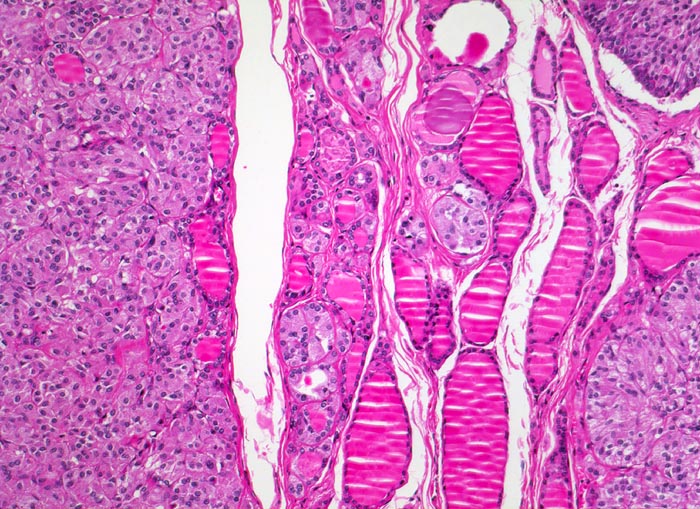

Das MTC metastasiert primär in die lokoregionären Lymphknoten. Bei 15% der Patient*innen liegen zum Zeitpunkt der Diagnose bereits Fernmetastasen in Lungen, Leber oder Knochen vor. Histologisch sind die Tumoren meist solide und bestehen aus monomorphen polygonalen und spindeligen Zellen (> 3821). Die Zellkerne zeigen das typische Pfeffer und Salz Chromatin neuroendokriner Zellen. Das Stroma enthält in ca. 50% der Fälle Amyloid.

• Mehrere, unscharf begrenzte, unbekapselte Tumorknoten mit desmoplastischem Stroma in ansonsten unauffälligem Schilddrüsenparenchym.

• Die Tumorinfiltrate bestehen aus soliden und kribriformen Verbänden spindeliger Tumorzellen.

• Mehrere Herde hyperplastischer C-Zellen im nicht-neoplastischen Schilddrüsenparenchym als möglicher Hinweis auf ein hereditäres medulläres Schilddrüsenkarzinom.

• Tumorzellen mit überwiegend monomorphen Zellkernen mit feinkörnigem Pfeffer und Salz Chromatin (Merkmal endokriner Zellen). Nukleolen sind nicht prominent. Reichlich eosinophiles Zytoplasma.